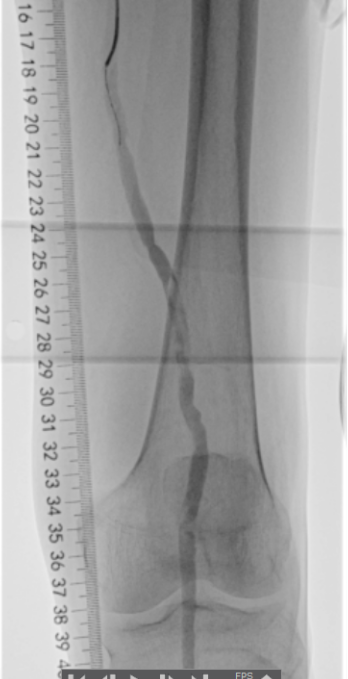

3.溶栓+球囊成形术后造影:

▲滑动查看更多

患肢动脉血栓清除,无明显残留狭窄,血流流速良好,足底动脉弓显影良好。